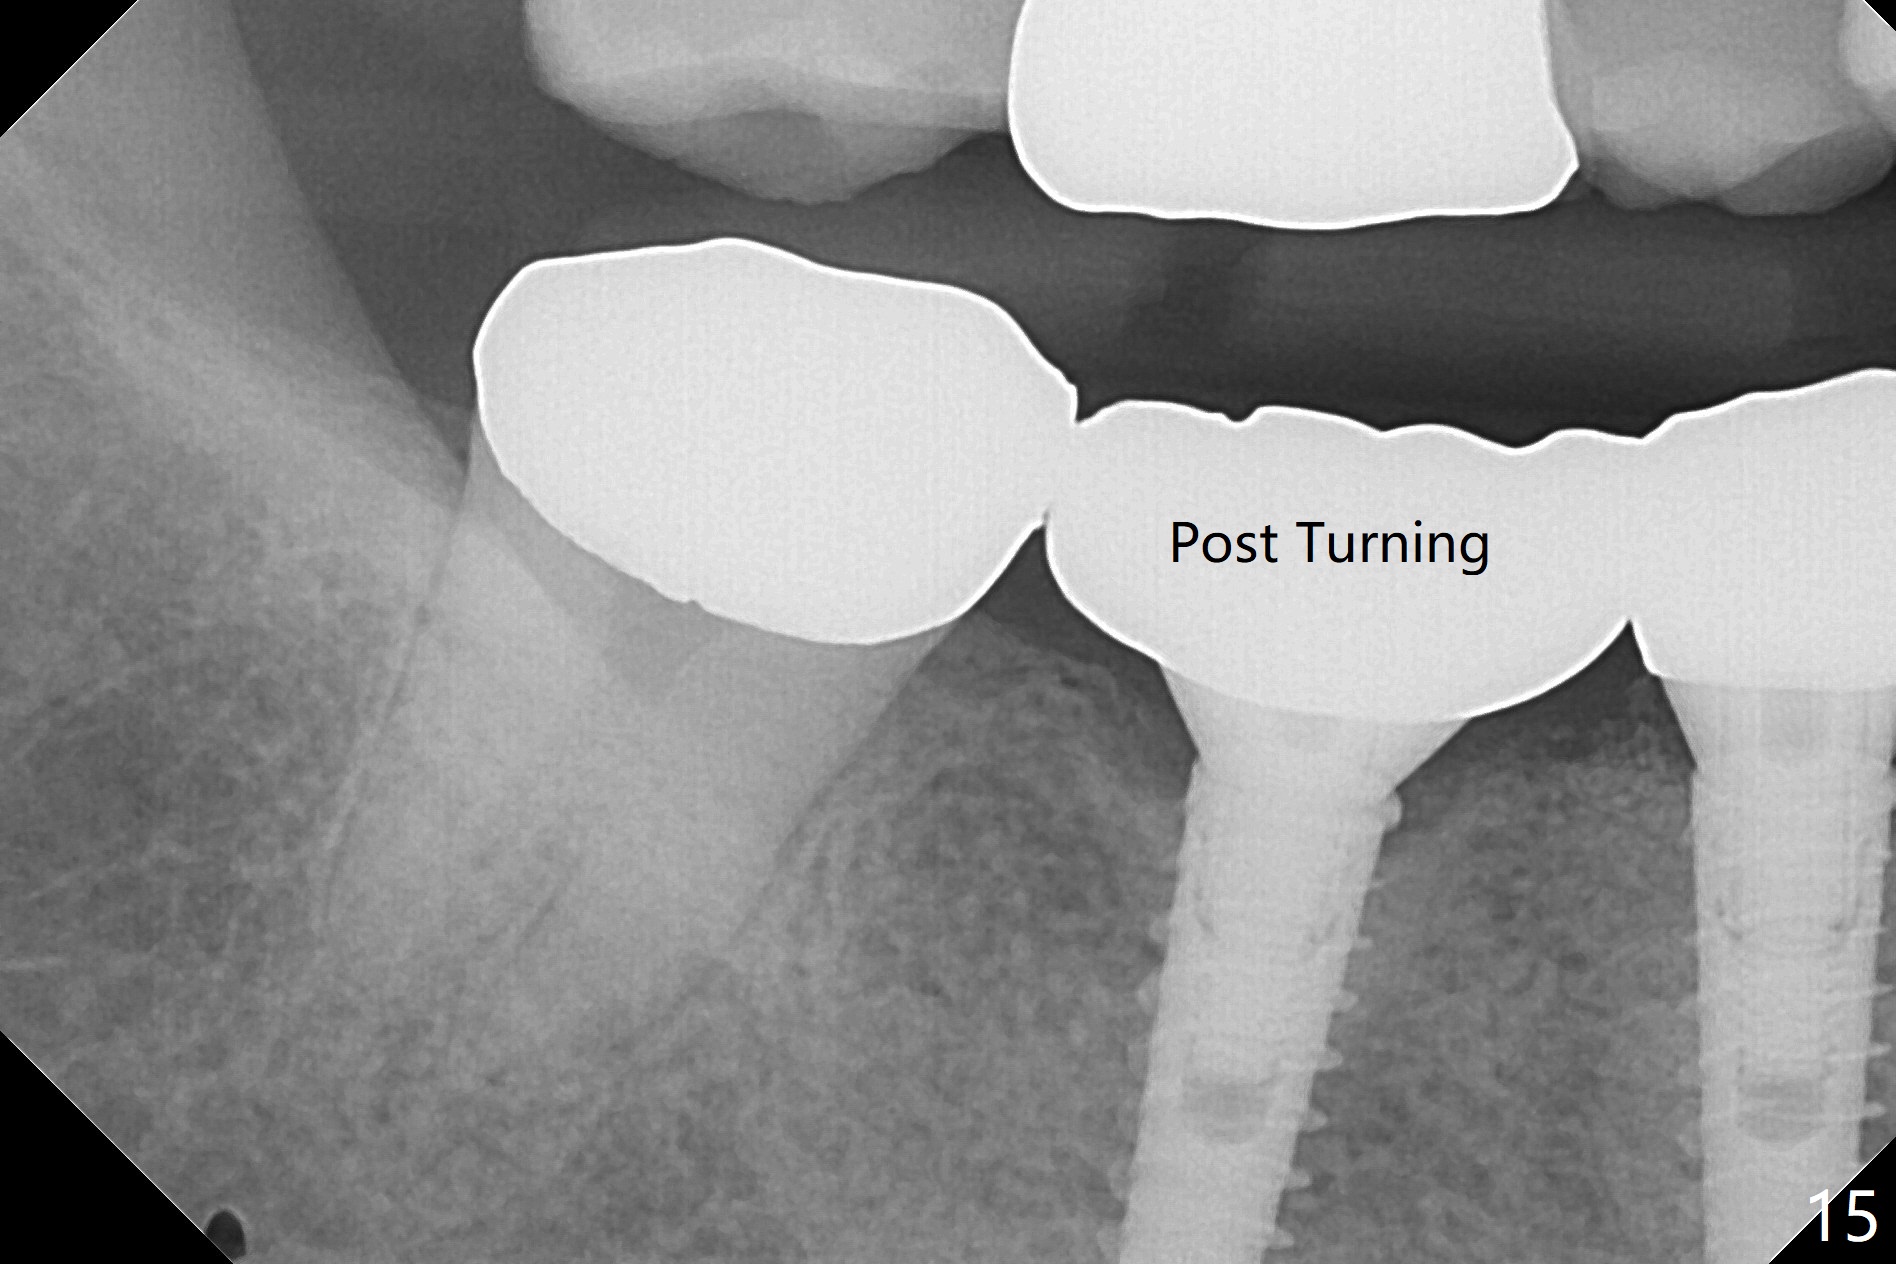

After incision, the ridge at #29 and 30 is found ~ 5 mm wide buccolingually. To place a 4x11 mm IBS implant at #30, the ridge is expanded using BEB technique (bone expansion and bending, Fig.1). It appears that the initial osteotomy at #29 is mesial (Fig.1 yellow dashed line: the distal surface of the root of the tooth #28). After moving the osteotomy distal, the final implant position at #29 (4x11 mm) is within normal limit (Fig.2). The bone at #29 seems to be not so dense that bending (using 1.6 mm drill) is not necessary (using Magic Split and Magic Expanders 3 and 3.8 mm). Later the implant at #30 (4x11 mm) is placed deeper (Fig.3). After placing bone graft around the implants/abutments and suturing, the ridge looks wider with apparent formation of the gingival bands around the abutments (Fig.4 *). Three months and a half postop, bone loss is minimal (Fig.5) and gingival bands forms around the abutments (Fig.6). Fig.7 is taken 1 month post cementation (panoramic X-ray). The patient chews normally 1 year (Fig.8) and nearly 2 years (Fig.9,10) post cementation. The crown at #31 needs recementation 2 years 7 months post #30 cementation; the incomplete seating of the abutment was noted for the first time (Fig.11). Five months later the patient is going to be retired and wants to travel abroad. After approval, the access hole was reopened; articulating paper shows under occlusion of the crown (Fig.12). Since the gap between the abutment and the implant is large, the abutment/crown complex seems to be necessary to be turned (Fig.13 curved arrow). The proximal surfaces of the crown need to be trimmed (straight lines). After turning, the crown sits down with screw tightening; the patient feels pain from the gingival cuff (Fig.14). After turning, the abutment appears to be completely seated (Fig.15). In fact the mesial and distal surfaces of the crown should have clearance from the neighboring teeth (Fig.14) so that pick-up impression is able to hold the crown/abutment complex securely (Fig.16: *). The crown is separated from the abutment after crown repair. They are seated together (loose connection) using the crown as a guide to seat the abutment. BW is taken without the crown. It appears that the abutment remains seated completely (Fig.17). The apical space is equal between #29 and 30 (Fig.17, as compared to Fig.5).